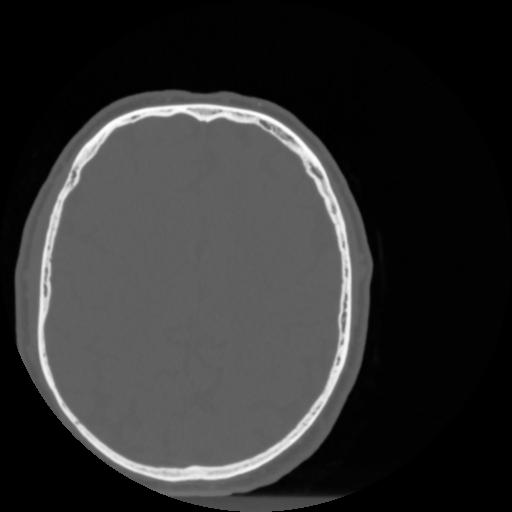

4 CEREBRO,,Vol,0.5,CEREBRO,,